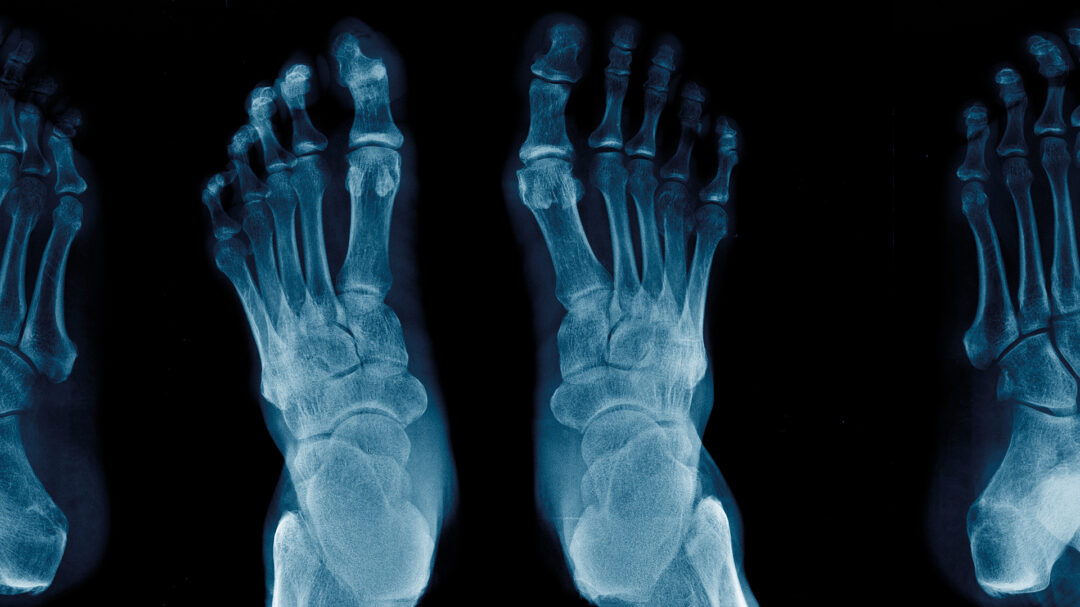

Το κότσι δεν είναι απλώς ένα οστικό εξόγκωμα (προσεκβολή) στο πλάι του πέλματός σας. Είναι μια μη ευθυγραμμισμένη μεταταρσοφαλαγγική άρθρωση. Η άρθρωση αυτή συνδέει το πρώτο μακρύ οστό του μπροστινού τμήματος του ποδιού (μετατάρσιο) με το πρώτο οστό (φάλαγγα) του μεγάλου δακτύλου.

Μερικές φορές, οι σύνδεσμοι που κρατούν αυτά τα οστά ευθυγραμμισμένα εξασθενούν, με αποτέλεσμα το πρώτο οστό στο μετατάρσιο να προβάλλει προς τα έξω. Η φάλαγγα στη συνέχεια μετατοπίζεται με κατεύθυνση επίσης προς τα έξω, και έτσι καταλήγετε να έχετε μια παραμόρφωση (βλαισό μεγάλο δάκτυλο) που προκαλεί περισσότερες δυσκολίες. Μεταξύ των δυνητικών προβλημάτων είναι: